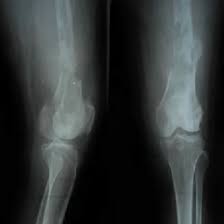

Radiopaedia's mission is to create the best radiology reference the world has ever seen and to make it available for free, for ever, for all. This helps radiologists correctly assess fractures, dislocations, or other abnormalities Mid and distal femur in ap projection

Femur ap purpose and structures shown proximal femur radiograph demonstrates the majority of the shaft, pelvic brim, obturator foramen, acetabulum, ischial spine, femoral head, and femoral neck It ensures the entire femur, from hip to knee, is visible and not obscured by rotation or other body parts Distal femur radiograph demonstrates the distal 2/3rd of.

Lateral view of femur demonstrating mid and distal bone

Lateral femur (mediolateral, with knee or hip included) cr location & positioning sid Lateral recumbent on affected side adjustments Flex knee 45°, epicondyles perpendicular, ir extends 2″ beyond knee This positioning produces a true lateral view of both the femoral head and neck.